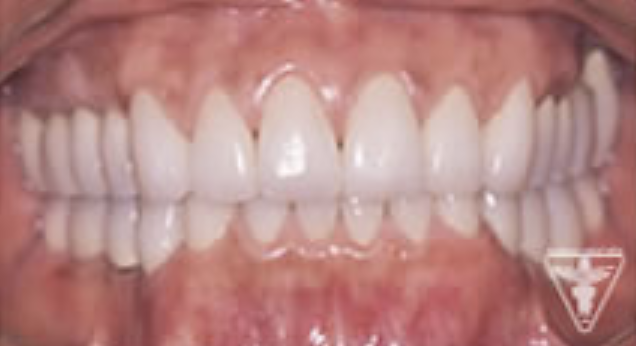

治療後

かみ合わせの深さを改善し、左下の骨を作り人工歯根で再構築しました。

前歯は、患者さんの希望でフルセラミックで対応しました。

「良く噛めて、自信をもって笑顔になれる。」と評価をいただきました。